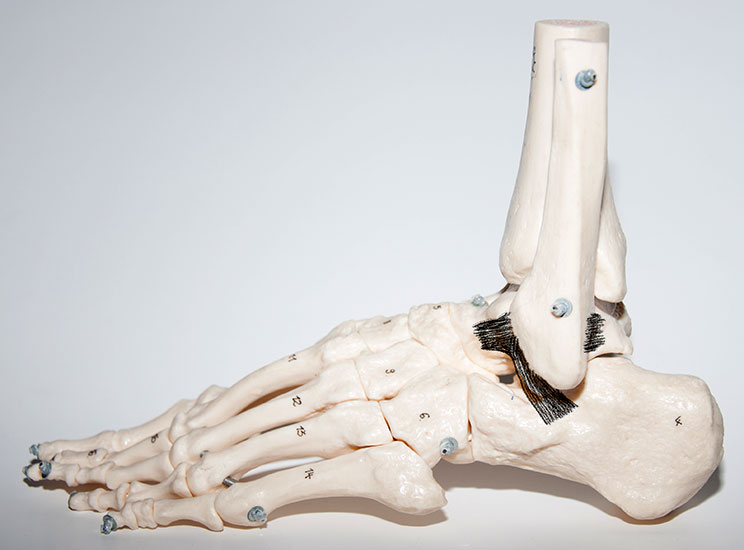

Die knöcherne Malleolengabel wird von Tibia und Fibula gebildet, die beiden Knochen werden durch die vorderen und hinteren Syndesmosenbänder, sowie die Membrana interossea stabilisiert. Der am häufigsten verletzte laterale Bandkomplex besteht aus dem Ligamentum talofibulare anterius (LTFA), dem Ligamentum fibulocalcaneare (LFC) und dem Ligamentum talofibulare posterius (LFTP) zusammen. Der typische Unfallmechanismus ist die forcierte Plantarflexion und Inversion des Sprunggelenks 7. Das LFTA ist das schwächste der drei Außenbänder und wird am häufigsten verletzt 8. Das LFTA limitiert die Plantarflexion und die Innenrotation 9. Das LFC ist 2-3,5-mal stabiler als das LFTA. In etwa 25 % der Fälle treten kombinierte Läsionen des LFTA und des LFC auf.